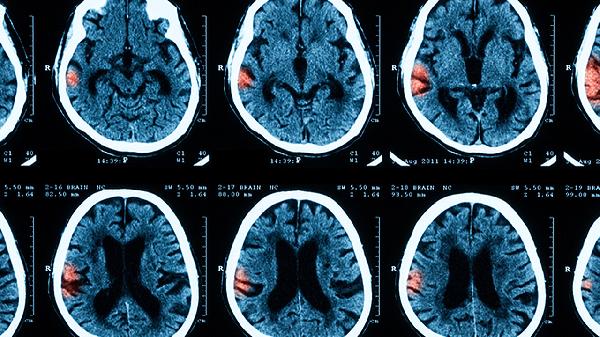

兩個(gè)月寶寶腦膜炎的早期癥狀包括發(fā)熱、拒奶、嗜睡,進(jìn)展期可能出現(xiàn)前囟膨隆、抽搐,嚴(yán)重時(shí)呈現(xiàn)角弓反張或昏迷。腦膜炎主要由細(xì)菌感染、病毒感染、免疫缺陷、圍產(chǎn)期感染及先天性畸形等因素引起。

約30%的嬰兒腦膜炎會(huì)出現(xiàn)局灶性或全身性抽搐,表現(xiàn)為肢體節(jié)律性抽動(dòng)、眼球上翻或面部肌肉痙攣。新生兒抽搐癥狀不典型,可能僅表現(xiàn)為呼吸暫停、面部抽動(dòng)或咀嚼動(dòng)作,需與正常驚跳反射鑒別。